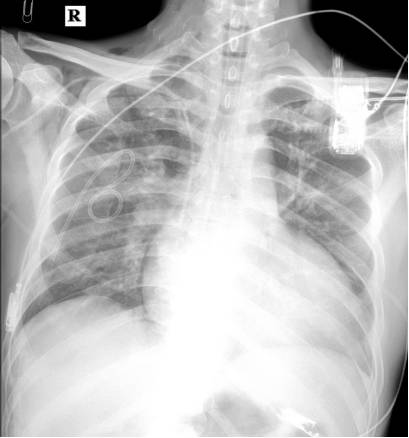

双肺湿性啰音明显减少,哮鸣音消失

23日 20:00(连续超滤25h) 尿量明显增多,停止血滤